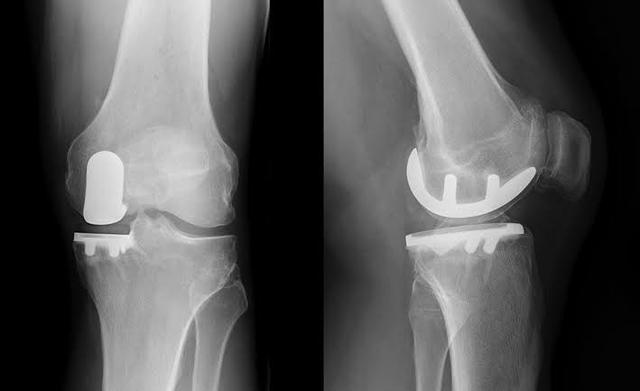

● Si les symptômes de l'articulation sont particulièrement sévères et que le patient a développé une...Déformations articulaires évidentesSi vous êtes incapable de marcher normalement, si vous ressentez des douleurs articulaires importantes lorsque vous marchez plus de 500 mètres et si vous êtes gravement affecté par des douleurs au repos ou pendant votre sommeil, il y a une indication pour une prothèse articulaire.L'arthroplastie du genou peut être le seul moyen d'aider complètement le patient.。

8. traitement chirurgical :Si les lésions du genou sont graves, elles peuvent également être réparées par chirurgie arthroscopique.

9. remplacement du genou :Si l'arthrose a entraîné une déformation évidente de l'articulation, qui affecte gravement le traitement de la vie du patient, le moment est venu de résoudre complètement le problème du patient par la mise en place d'une prothèse de genou.

Apparition tardive : articulations artificielles pour soulager la douleur sévère

Aux stades avancés de la maladie, le cartilage du patient est presque usé. Sans l'amortissement du cartilage, les os frottent directement l'un contre l'autre. À ce stade, les seules options sont de remplacer l'articulation par une prothèse ou de procéder à une arthrodèse, qui est rarement utilisée car elle peut affecter gravement la mobilité du patient après l'opération.